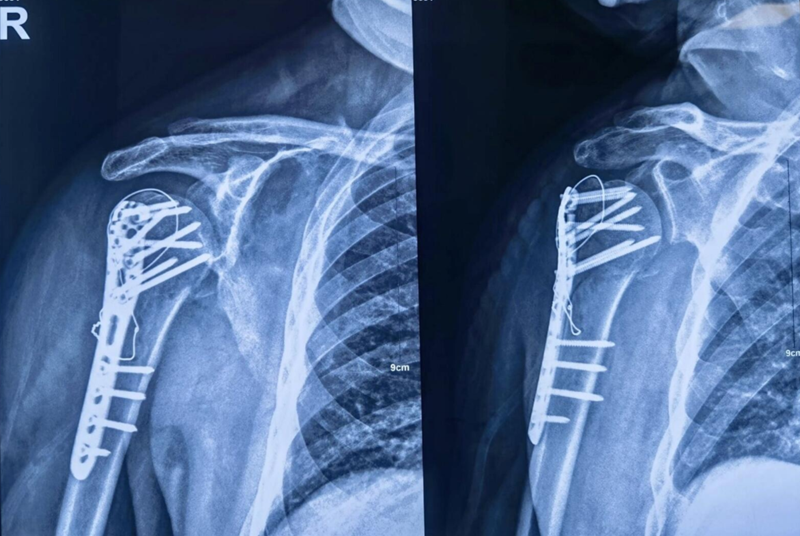

十二、典型病例

Xxx,男,65岁,右肱骨近端四部分骨折一周。

图16 术前X片

肩前外侧劈三角肌入路,三角肌前束和中间束肌肉间隙进入,双套固定技术加强固定。

图17 术中

术中C-臂检测:

图18 肱骨距螺钉固定确切

术中大幅度肩关节屈伸与外展内收活动,提示骨折坚强固定。

图19 术后X片